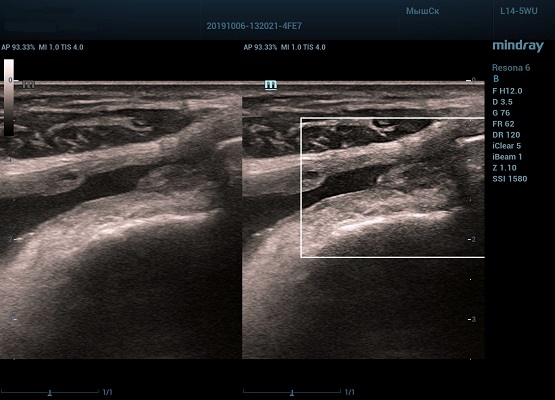

Производители ультразвуковых приборов постоянно работают над облегчением рабочего процесса доктора ультразвуковой диагностики, на этот раз компания Mindray добавила в экспертные и премиум аппараты, такие как Resona 6 и Resona 7, функцию HD Scope.

HD Scope позволяет достигать поразительной разрешающей способности выбранной зоны сканирования, при этом улучшая как детализацию, так и контрастность изображения. Помимо пространственного разрешения мы получаем преимущество и по разрешению во времени. Прибор получает огромное количество нативных изображений практически одновременно, и при сборе итоговой картины не происходит смещения объекта под датчиком, а значит и нет размывания изображения. Все участки раздела фаз, каждый контур образования теперь видны, мы все ближе к идеальной картинке.

Как он работает? Особенностью платформы ZST+, на которой построены приборы Mindray Resona, является так называемое многолучевое сканирование. В отличие от обычного датчика, который получает изображение в виде прямого эхо, датчики приборов этой серии проводят многолучевое сканирование каждым элементом с огромной скоростью, получая огромное количество данных. Затем происходит сложная постобработка и сбор из множества «многолучевых» снимков идеальной картинки.

Вторая особенность ультразвуковых машин данной линейки — это изменение расчетных констант распространения ультразвука, таким образом прибор перебирает для каждой ткани свои значения скоростей волны и пересчитывает каждую точку, делая менее выраженным поглощение по глубине. Эти особенности позволили использовать без фокусные технологии сканирования. Функция HD Scope позволяет использовать эти ресурсы для исследование небольшой области, значительно увеличивая качество изображения.